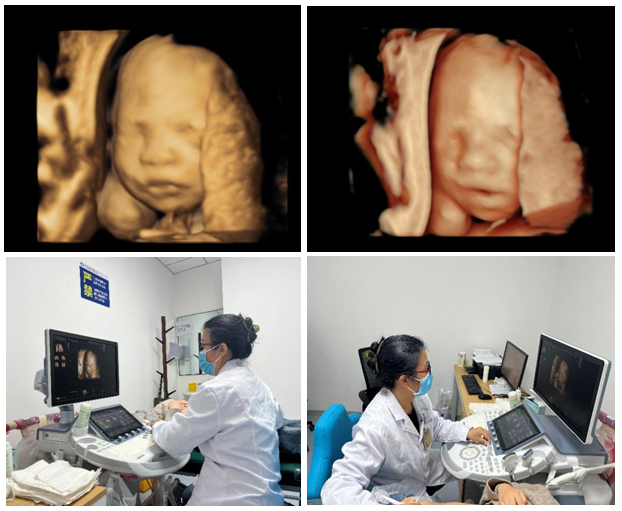

10月30日,五楼自拍 超声诊断中心西咸院区开展第一例胎儿心脏彩色多普勒超声检查,同时开展了超声诊断中心西咸院区第二例输卵管超声造影。

10月31日,超声诊断中心西咸院区为一位29岁的二胎孕妇,成功开展胎儿四维系统彩色多普勒超声检查,这是西咸院区的第一例胎儿四维系统超声检查。